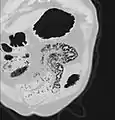

استرواح الأمعاء في التصوير المقطعي المحوسب أثناء نقص التروية المعوي. نافذة الرئة لتمثيل أفضل لرواسب الغاز في جدران الأمعاء.